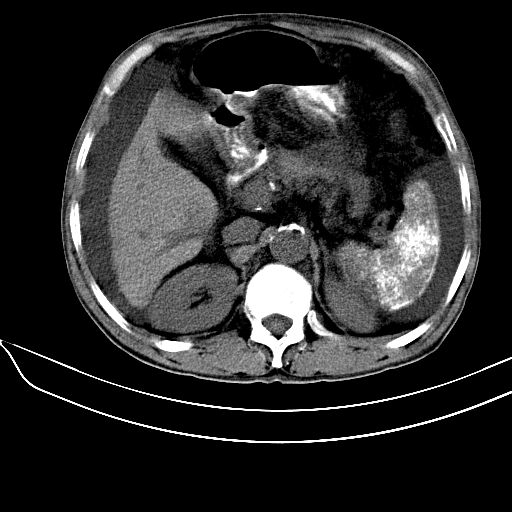

标题: CT6807:脾脏病变,应考虑什么?

患者64岁,女,腹胀。腹水脾脏内多发高密度,ct值为126hu。

患者64岁,女,腹胀。腹水。脾脏内多发高密度,ct值为126hu。

肝硬化可以肯定,但是脾脏不是很大,要诊断血吸虫病是不是还要结合流行病学,有没有疫情,疫区接触史;